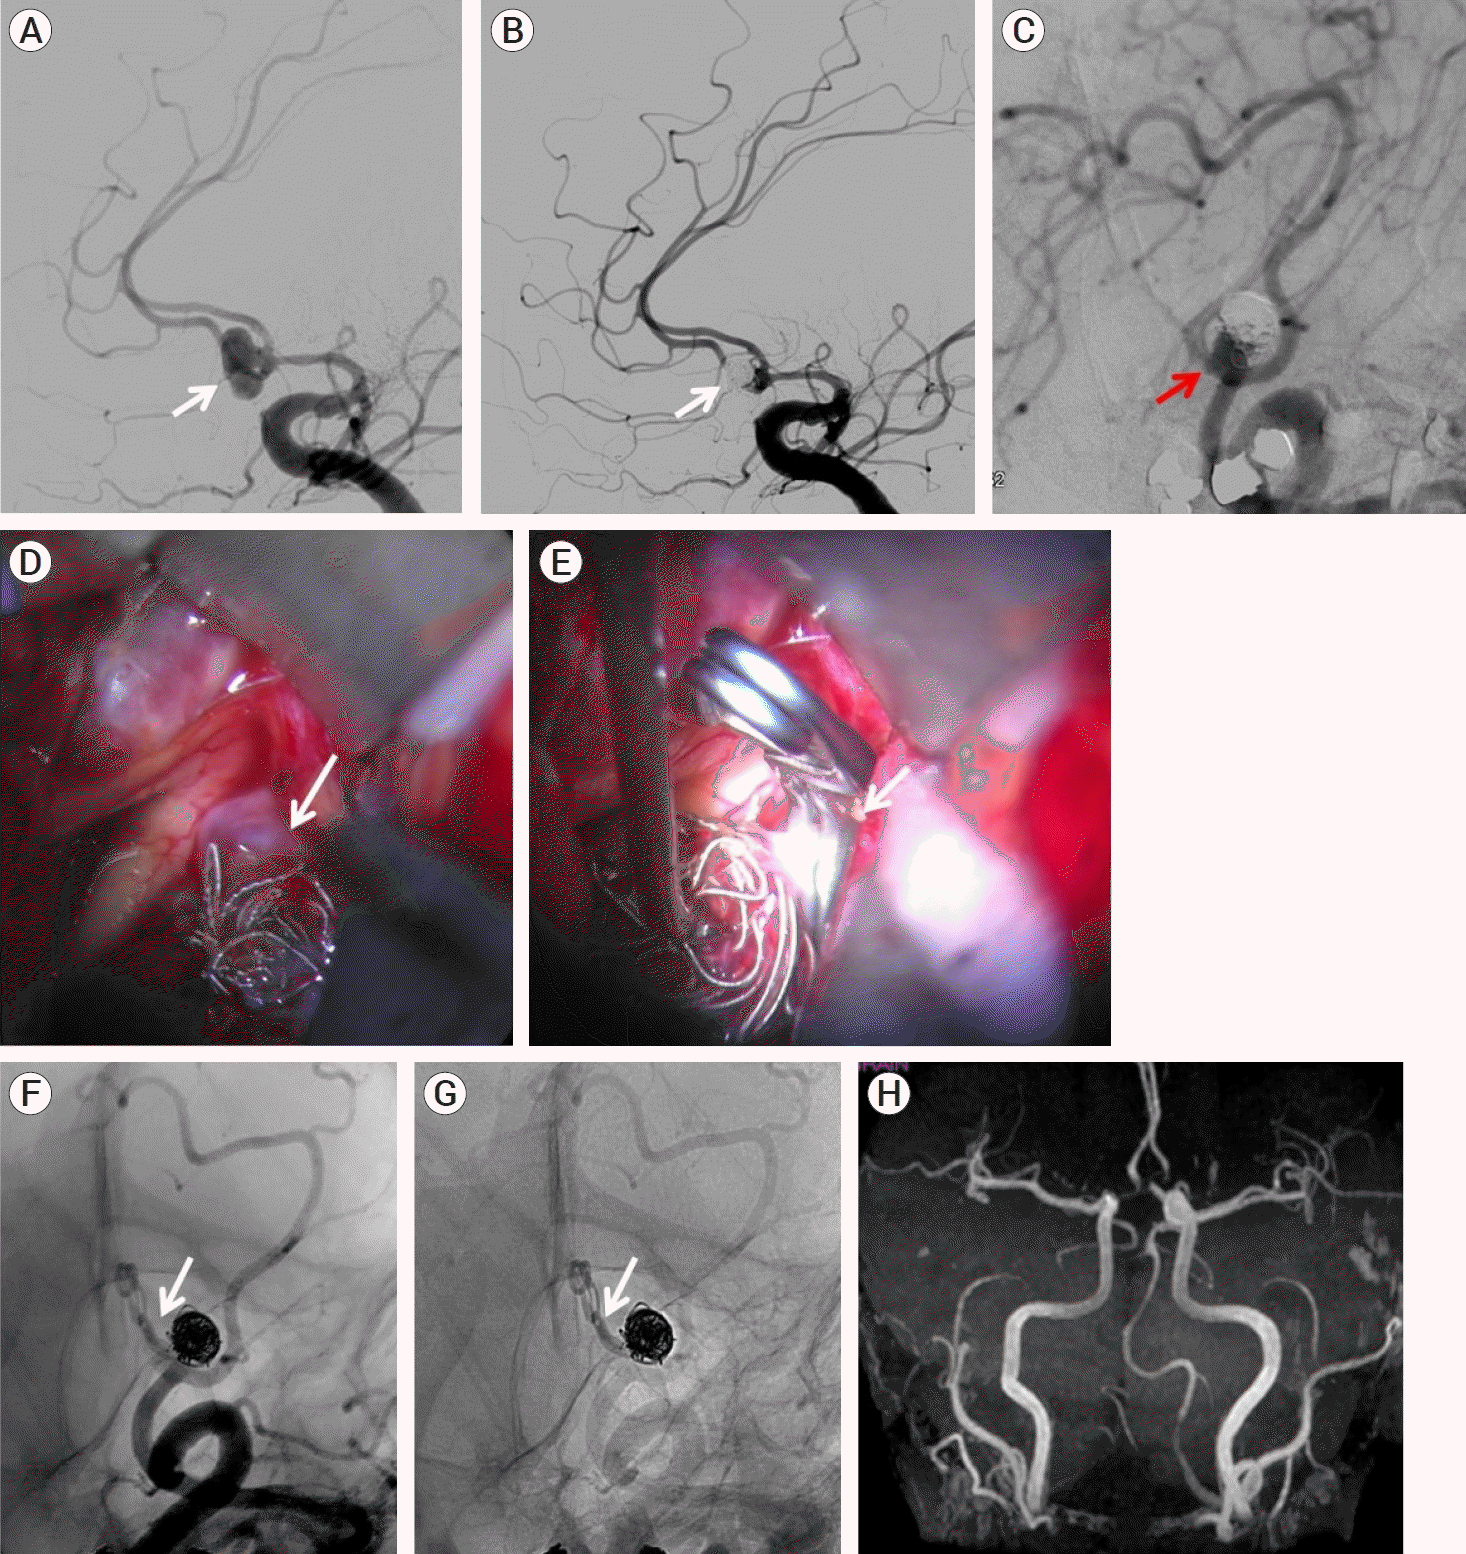

A 47-year-old female patient presented with SAH due to a ruptured narrow neck anterior communicating artery (ACoA) aneurysm (A, white arrow). The aneurysm had an irregular shape, and the Dome/Neck ratio was 2.33. The patient was initially treated with an endovascular approach using Guglielmi Detachable Coils (GDCs) and full occlusion was achieved (B, white arrow). In the angiographic follow-up nineteen months later, recanalization of the neck alongside with coil compaction (C, red arrow) was observed, and the patient was admitted for microsurgical retreatment. Right frontotemporal craniotomy was performed, and the aneurysm neck was carefully dissected (D, white arrow). A 45° angled clip was placed at the aneurysm neck beneath the coil mass (E, white arrow). A 100% obliteration rate was accomplished, as demonstrated in postoperative DSA (F, G, white arrow) and follow-up MRA (H). The patient had an uneventful recovery (post-clipping mRS 0).

(A) DSA illustrates a ruptured narrow neck ACoA aneurysm (white arrow). (B) Complete embolization of the aneurysm has been initially performed (white arrow). (C) FU angiogram shows recanalization of the neck (red arrow). (D) Intraoperative view illustrates the neck remnant. (E) A 45° angled clip has been placed below the coil mass (white arrow). (F, G) Postopetrative DSA shows optimal positioning of the clip (white arrow). (H) Postoperative MRA illustrates complete patency of the A2 vessels. DSA, digital subtraction angiography; AcoA, anterior communicating artery; FU, follow up; MRA, magnetic resonance angiography